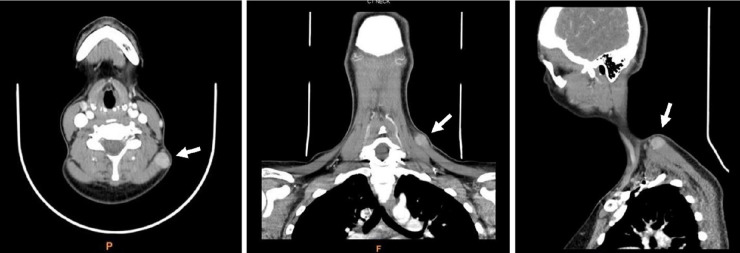

Inflammatory myofibroblastic tumor (IMT) of the soft tissues of the neck is a rare pathological entity. We present the case of a 32-year-old patient who had a painful, slowly enlarging mass in the neck's soft tissues. Radiological examination revealed a well-defined, dense lesion. The mass was surgically removed through local excision. Immunohistological analysis confirmed the diagnosis of IMT. After nearly 2 years of follow-up, there was no evidence of recurrence or distant metastases. In conclusion, although IMT of the soft tissues of the neck is uncommon, it should be considered in the differential diagnosis of neck tumors. Further research is necessary to understand the pathogenetic mechanisms of IMT, which could lead to the development of more effective treatments for this tumor.